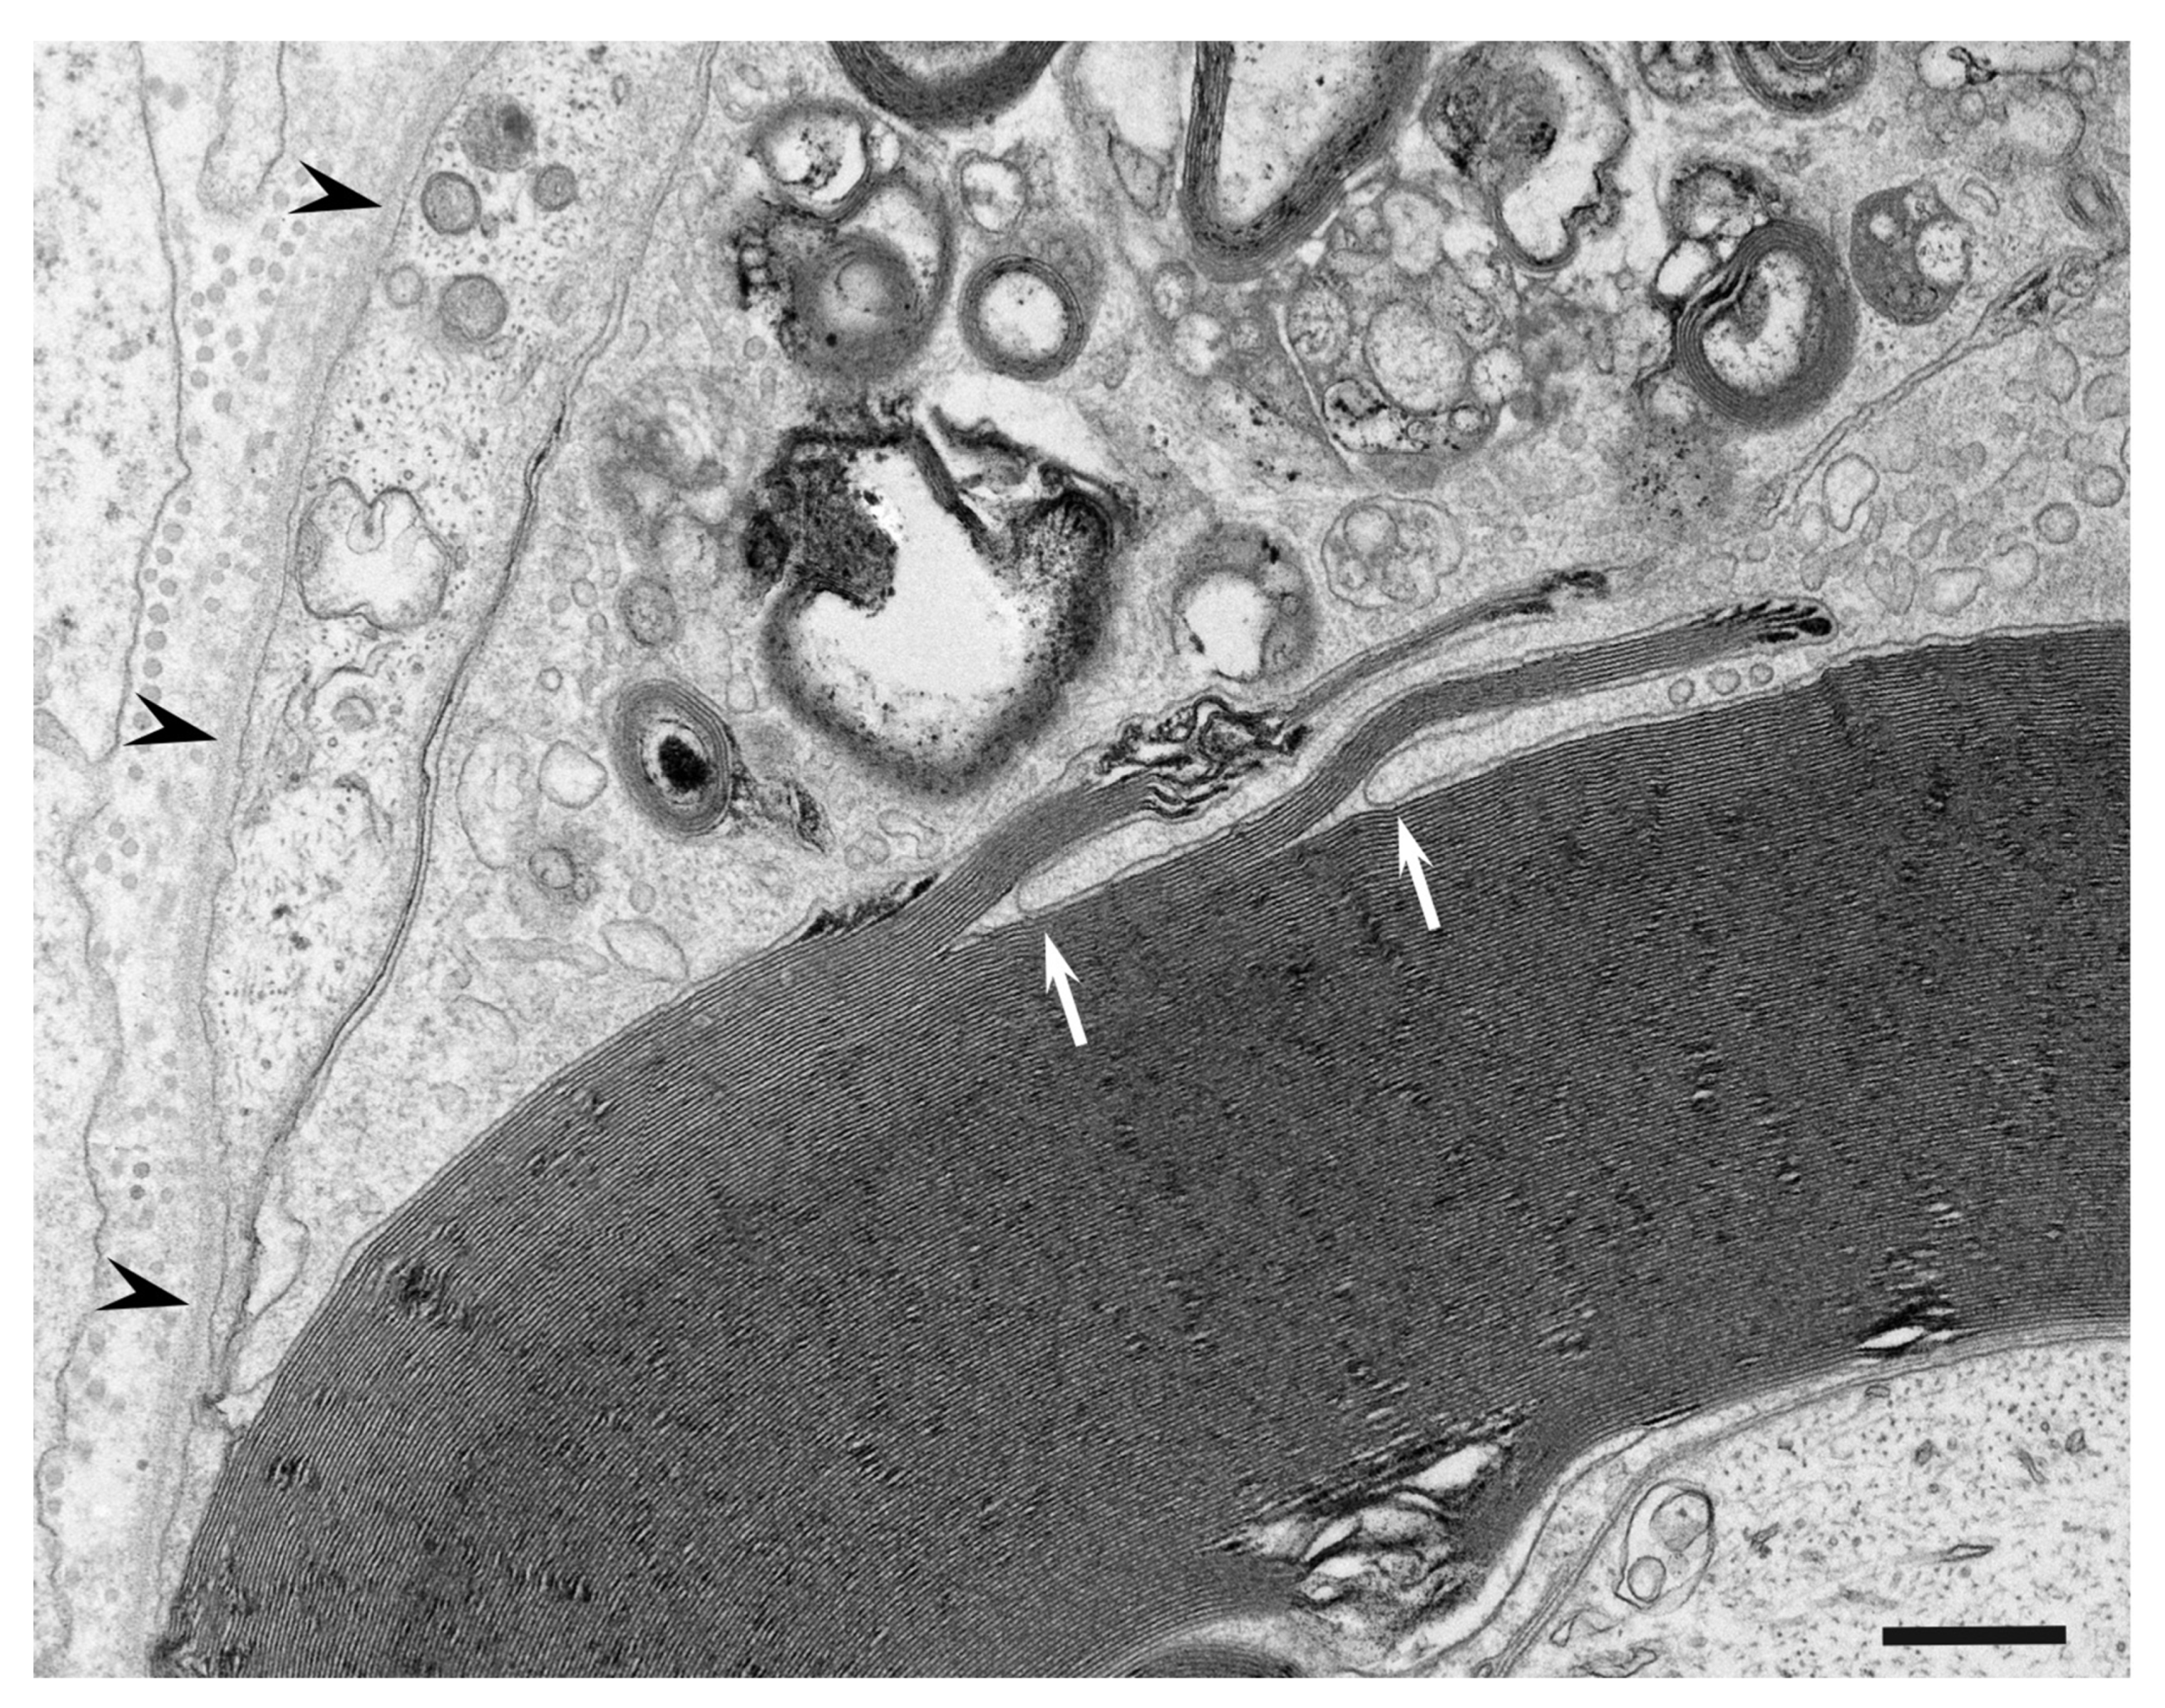

3. Morphology of Macrophages in Demyelination